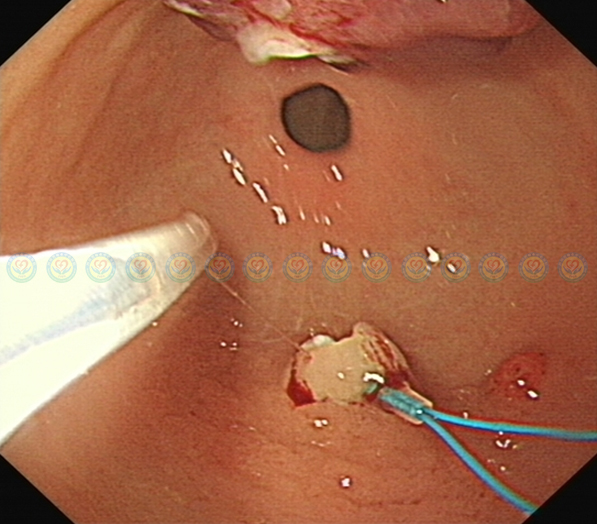

送入高频电圈套器,在结扎环上方0.5cm以上电切。

一次性完整切除肿块,无残留,无出血。术后患者无不适。